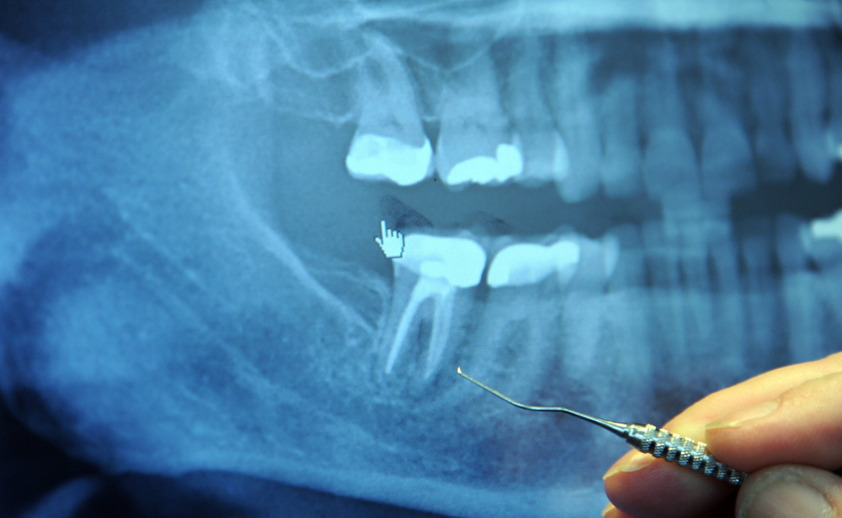

치과 가기 싫어하는 사람이 많을 겁니다. 치과는 방문 시기가 빠를수록 고통과 비용을 줄일 수 있다는 걸 알면서도 게으름과 두려움이 동시에 발목을 잡아 치과 방문 시기를 늦어지게 만들죠. 이렇게 늦어진 대가는 고통을 배가시키고 다시는 치과에 오지 않도록 관리하겠다는 다짐을 만들지만 결국 반복되는 경험을 합니다. 이런분들을 위해 치과의사가 치과에 오지 말라며 알려준 가글 방법이 있는데 어떤 방법인지 소개해드리겠습니다.